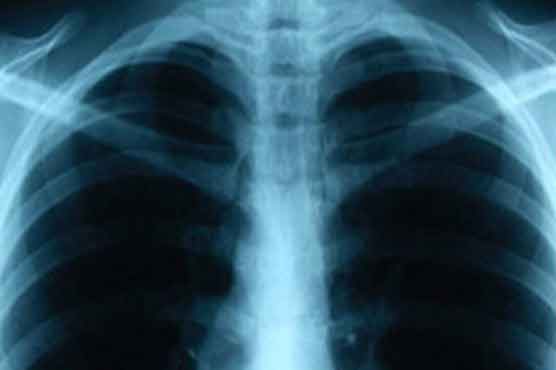

Tuberculosis is a disease caused by a bacterium, called Mycobacterium tuberculosis, which typically attacks the lungs but can also affect the kidney, spine and brain.